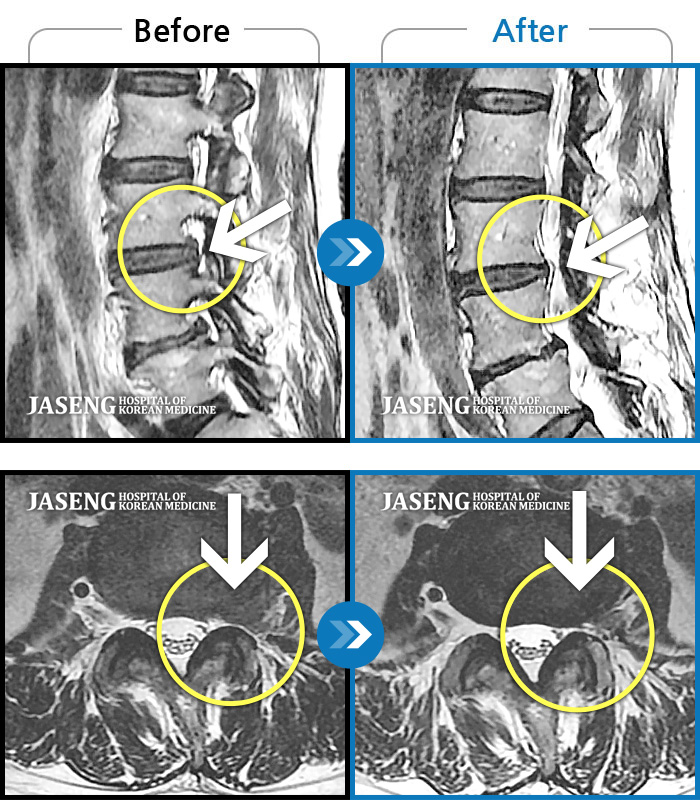

Before

After

환자에게 사전 동의를 받아 동일 조건에서 촬영되었습니다.

개인에 따라 치료 후 부작용이 발생할 수 있으니 의료진과 상담 후 치료를 진행하시기 바랍니다.

좌측 허리와 골반이 아프고, 좌측 다리에 통증과 저림이 있었다.